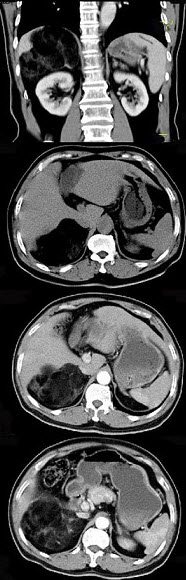

男,59岁,右侧腰背酸痛,CT检查如图所示,应诊断为( )

A、右肾上腺腺瘤

B、右肾上腺转移瘤

C、右肾上腺髓样脂肪瘤

D、右腹膜后脂肪瘤

E、右肾血管平滑肌脂肪瘤

点击查看答案